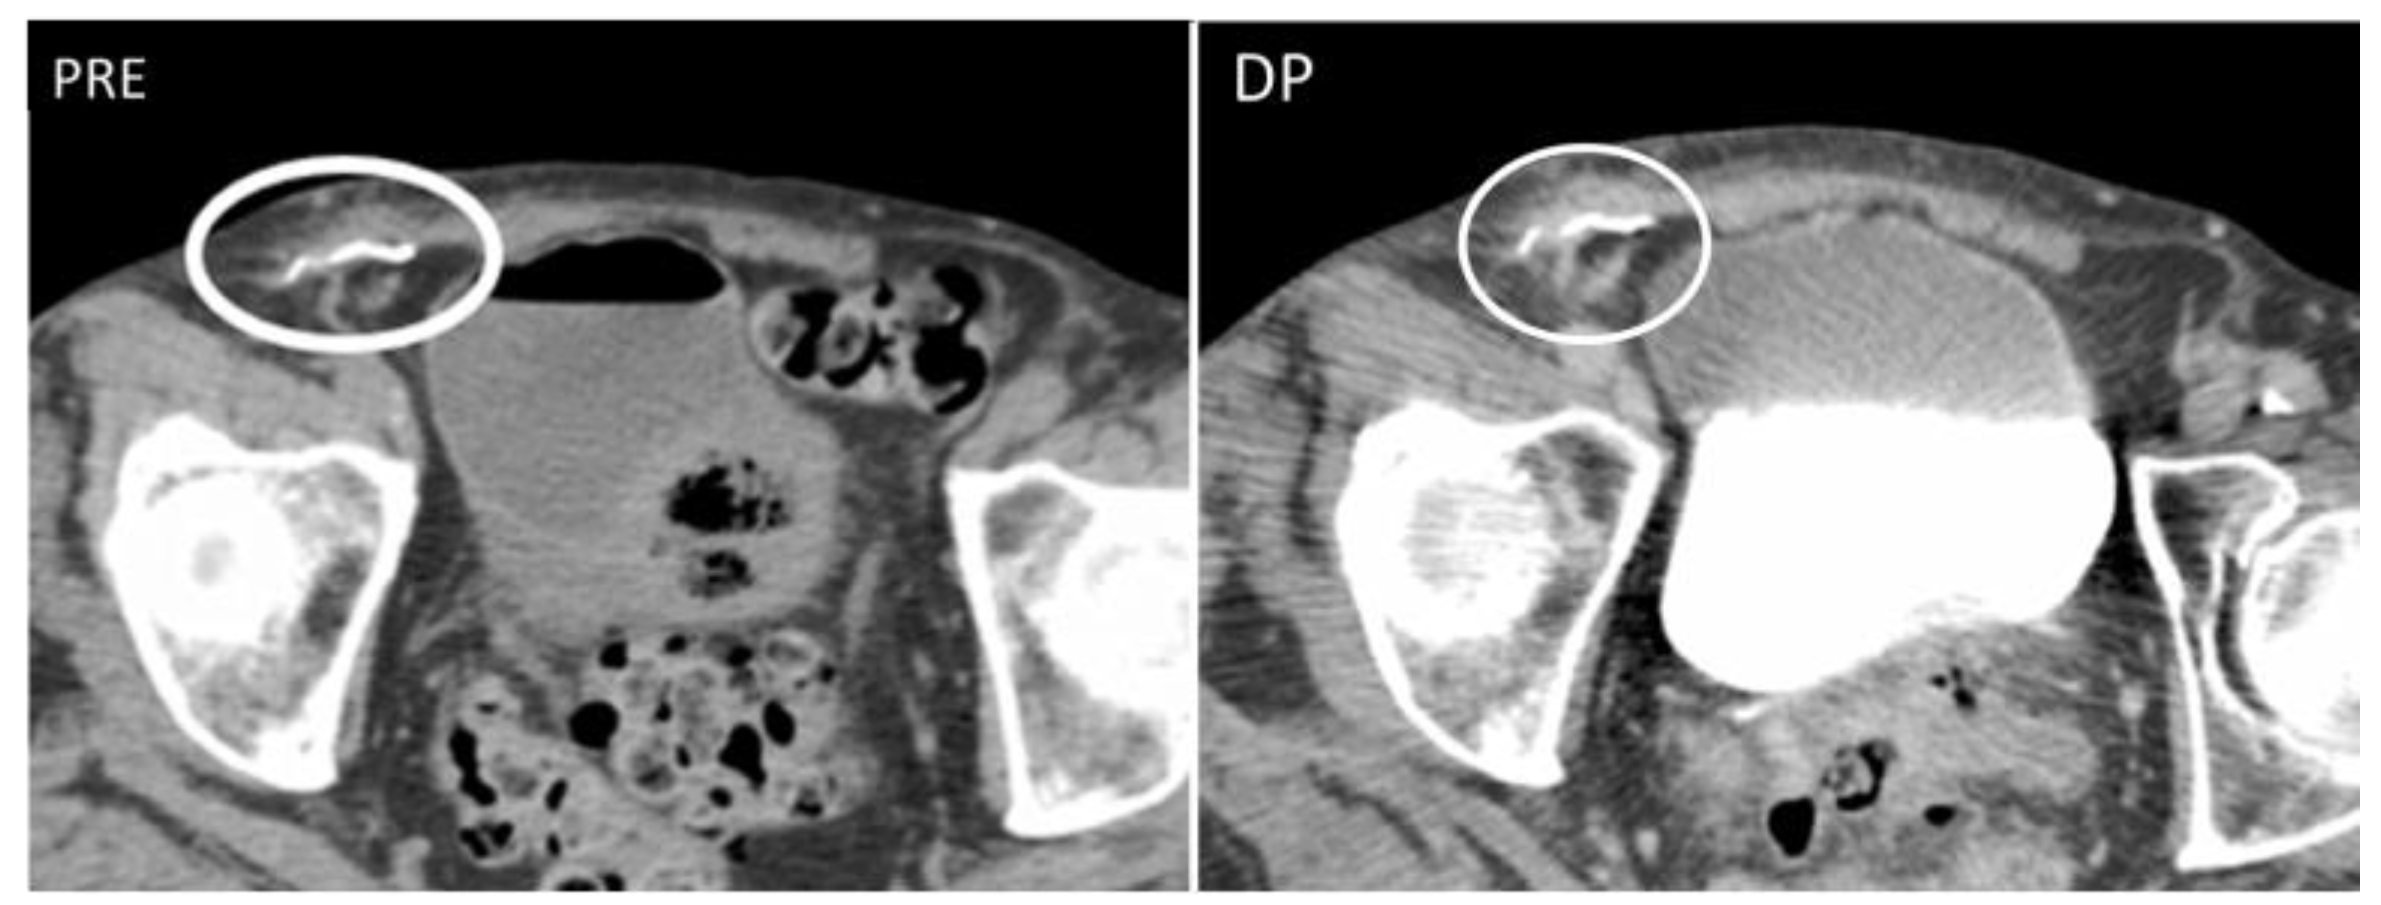

Figure 3. Granuloma occurring along a surgical mesh for an inguinal hernia repair. Axial CT on unenhanced (image on the left) and delayed phase at 10 min (image on the right) shows the formation of a nodular, fibrotic mass, with uptake contrast in delayed phases around a surgical mesh (circle).

Granulomas are protective responses to destroy or sequester particles that are deemed harmful to the body, frequently seen in the context of chronic infections, inflammatory diseases, and foreign bodies. On US, retained foreign bodies are usually hyperechoic with posterior acoustic shadowing, although their appearance depends on their content [3]. As granulomas develop, they appear as well-defined nodular lesions with a peripheral hyperechoic, ill-defined halo that slowly becomes hypoechoic and then hypervascular [3,8]. CT demonstrates a soft tissue lesion with punctuate or gross calcifications, surrounded by fat stranding [5]. Slight peripheral contrast uptake is seen in chronic stages (Figure 3).